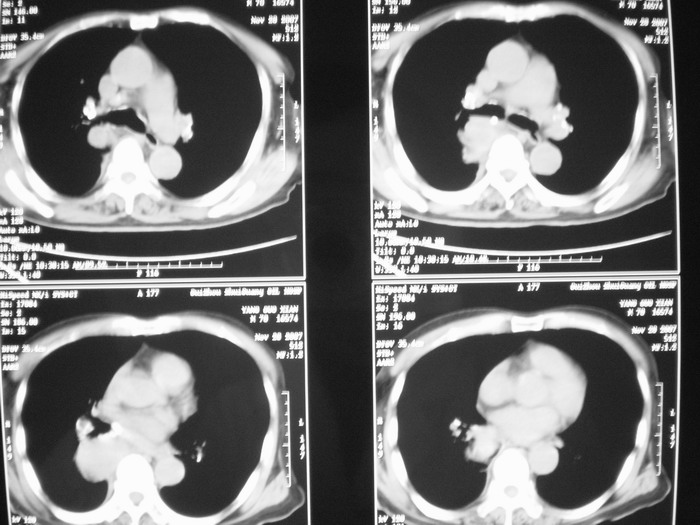

m、70y,反复咳嗽2月。请各位同仁给定位1、(肺?,纵隔?)2、定性。感谢!!

右后纵隔良性占位性病变,神经原性肿瘤可能性大,就其形态看,高密度囊肿待排,建议mri检查。

考虑右后纵隔良性肿瘤,以神经纤维瘤可能性大。

右下肺纵隔旁较大 均匀密度肿块,部分边缘植入纵隔,气管明显受压 变形。支持:后纵隔肿瘤!首选:神经源性!不支持肺内肿瘤原因:1 肿瘤位于下叶支气管及背段支气管开口区,但未侵犯支气管,只是受压表现。2 纵隔内未见肿大淋巴结。3 肺内未见阻塞性肺炎。

支持后纵隔肿瘤,病灶大体呈“滴状”与支气管关系密切,考虑:1.高密度支气管囊肿,2.神经纤维瘤。增强有鉴别意义。